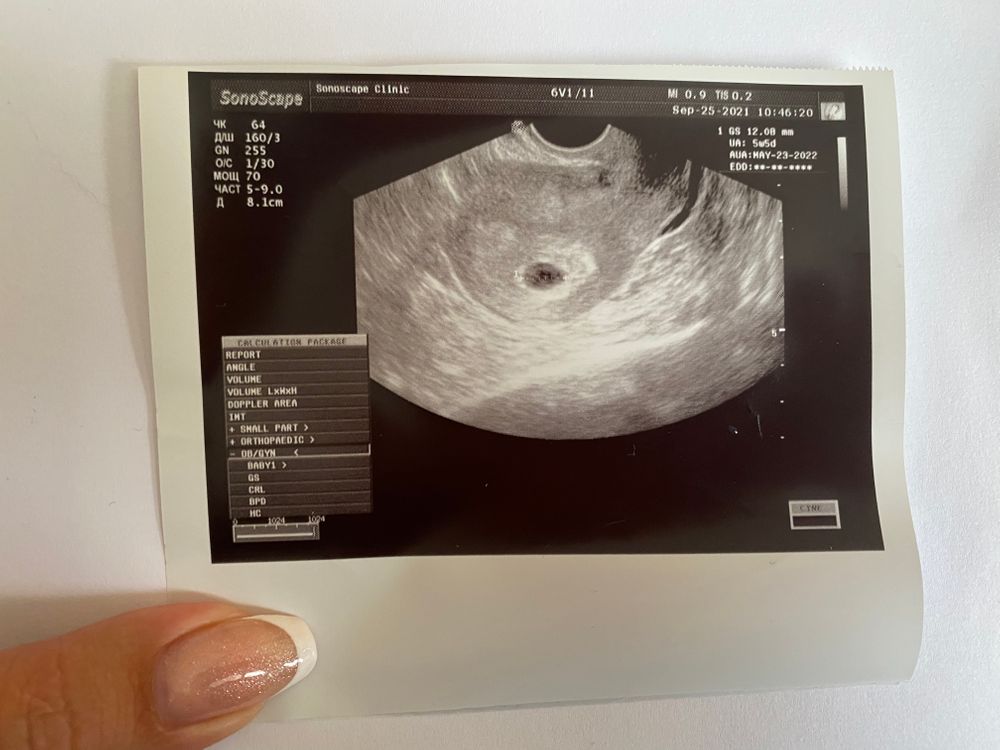

25.09 узи

Планирование 4 (цикл от 13.08.2021)Ураааа малыша нашли в матке) сказали все хорошо, яйцо правильной формы, есть желточный мешочек. Поставили срок 5.5 по узи. По месячным сейчас 6.2, но цикл не стабильный, овуляцию не отслеживала)

Насколько поняла с фотки, а то узи было между пациентами быстренько, то размер ПЯ 12мм. Надеюсь что все как надо)))